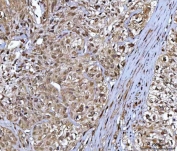

IHC staining of FFPE human colorectal adenocarcinoma tissue with NR5A2 antibody. HIER: boil tissue sections in pH8 EDTA for 20 min and allow to cool before testing.

IHC staining of FFPE human parotid acinar cell carcinoma tissue with NR5A2 antibody. HIER: boil tissue sections in pH8 EDTA for 20 min and allow to cool before testing.

IHC staining of FFPE human bladder urothelial carcinoma tissue with NR5A2 antibody. HIER: boil tissue sections in pH8 EDTA for 20 min and allow to cool before testing.